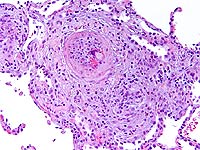

Blood cultures were positive for fungi in hyphae form (Figure-3) and fungal culture from BAL were positive for Scedosporium prolificans.

Diagnosis

Disseminated Scedosporium prolificans infection.

Scedosporium was first identified as a human pathogen in 1984. About 10% of patients with cystic fibrosis are colonized with this organism. It can be isolated from soil and fresh water. Disseminated infections can occur in immunocompromised with risk factors: leukemia, bone marrow and solid organ transplants, and states of impaired cellular immunity. In most case reports high dose steroids, tacrolimus, or cyclosporine were implicated. Clinical manifestations resemble Aspergillosis.